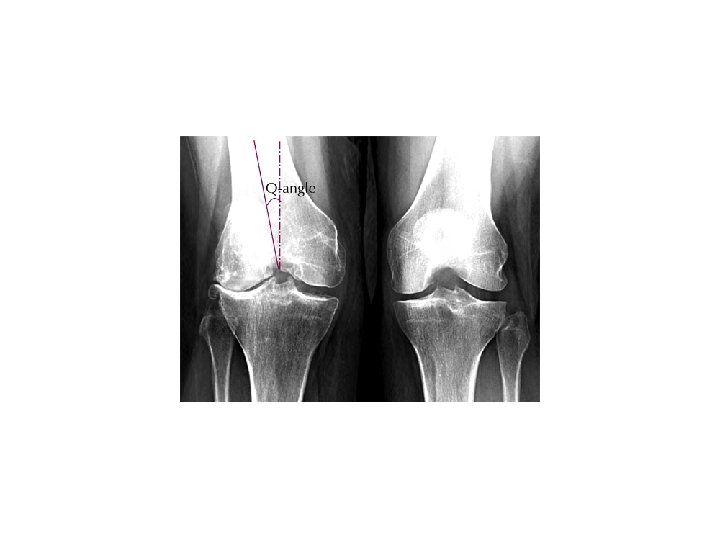

ALIGNMENT • Alignment: Anatomic relationship between bones on x-ray – Bone alignment vs other side – Bone alignment relative to proximal and distal bones • Normal x-rays should have normal alignment • Fractures and dislocations may affect the alignment on the x-ray